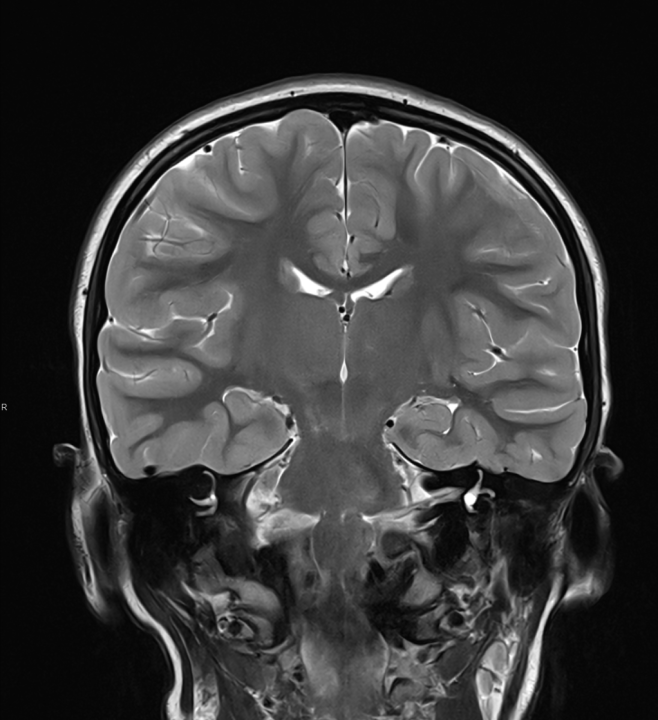

FOTO Ako su vam potrebni specijalistički pregledi mamografija, RTG, UZV, CT i MR, koji se inače koriste za dijagnostiku velikog broja zdravstvenih problema, možete ih obaviti već danas ili sutra. Vodite računa o vašem zdravlju i zakažite pregled u Poliklinici Affidea Vita u Šibeniku na vrijeme!